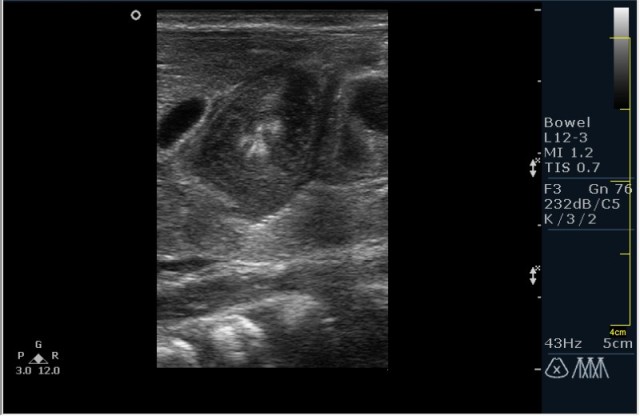

Ребёнок 1 месяц 10 дней от родy, с отсуствием прибавки в весе.

Hypertrophic pyloric stenosis.

Criteria:

1.Pyloric channel > 12 mm in length

2.Muscular layer thickness > 3-4 mm

3.Donuts sign at transverse scanning